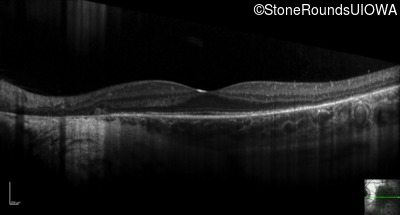

Optical Coherence Tomography - Right - 20/16

Exemplar / OCT Stack

Optical Coherence Tomography - Left - 20/12.5 -2